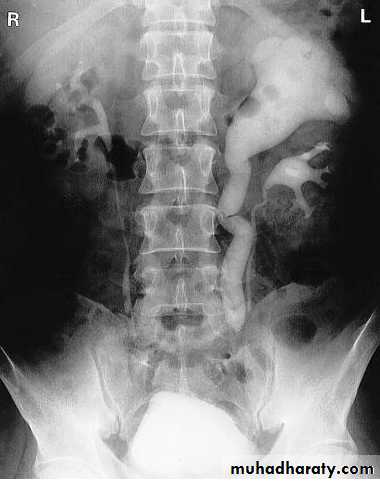

Laterally displaced ureters

Medially displaced ureters